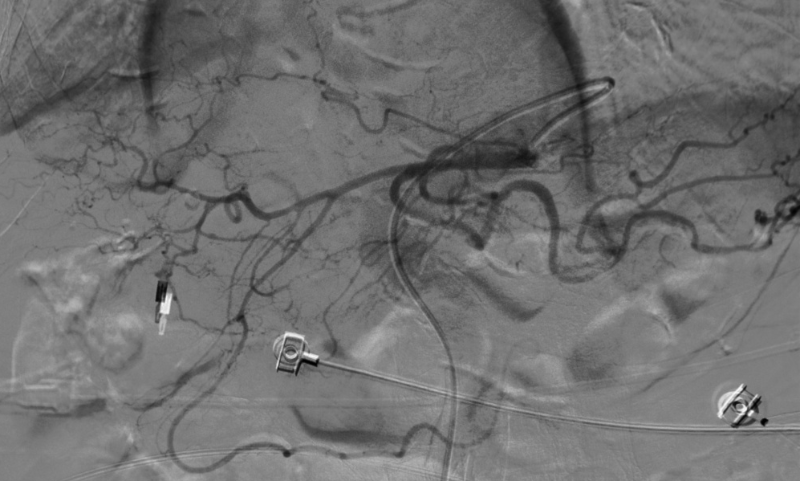

造影显示肝总动脉发出胃十二动脉及肝左右动脉。但胃十二指肠多处弯曲,微导管进入胃十二指肠动脉远端困难,更换成超细导丝后最后将微导管送入胃十二指肠动脉远端。

经微导管注入栓塞剂到胃十二指肠动脉全程,造影显示胃十二指肠动脉栓塞彻底,肝内动脉分支血运良好无副栓塞。